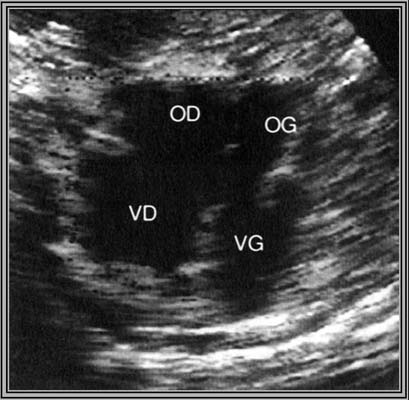

*Canal atrio-ventriculaire partiel : Il existe deux appareils auriculo-ventriculaires distincts.

- Appareil mitral déplacé à l’apex du VG se trouvant ainsi à la même hauteur que la valve tricuspide.

- S’y associe soit une CIA type ostium primum, une CIV postérieure au contact des valves AV et/ ou une fente de la grande valve mitrale.

Intérêt du codage couleur qui facilite l’identification des communications intra-cardiaques.